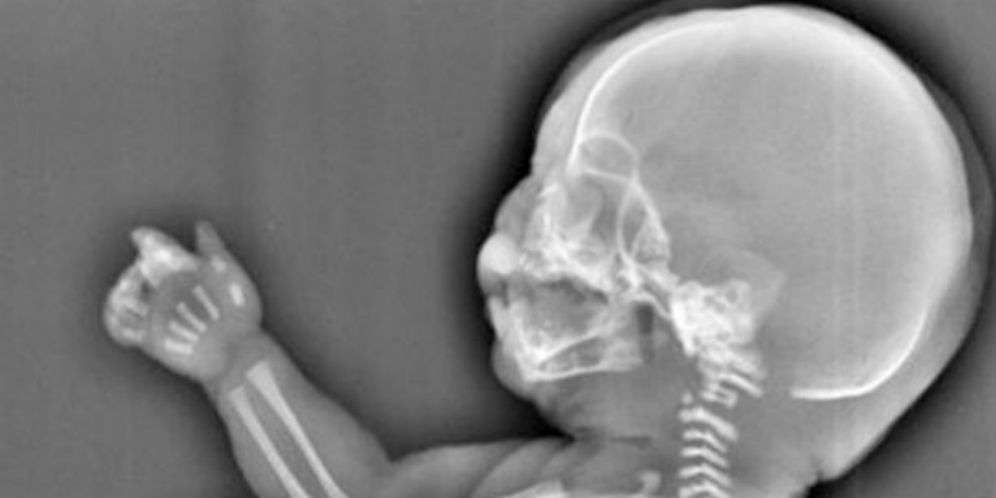

Dream - Seorang perempuan muda terpaksa menggugurkan kandungan berusia enam bulan setelah dokter mengatakan janin yang ada dalam rahimnya tumbuh tidak normal. Dia diberitahu bahwa janin yang dikandungnya memiliki bentuk kaki mirip putri duyung.

Perempuan berusia 23 tahun mengambil tindakan drastis itu setelah melihat hasil scan di PusatKesehatan Perempuan dan Anak di Yichang City di Provinsi Hubei, China Tengah.

Hasil scan menunjukkan janin yang dikandungnya memiliki kaki yang lebih mirip ekor. Janin tersebut juga tidak memiliki kandung kemih dan organ hatinya tersumbat.

Dream - Dokter di rumah sakit mengatakan kepada calon ibu bernama Wu bahwa calon bayinya itu menderita kondisi langka yang dikenal sebagai sirenomelia, atau 'Sindrom Mermaid'.

Itu adalah kelainan bawaan langka di mana kedua kaki menyatu sehingga memberi kesan penampilan seperti ekor putri duyung.

Wu langsung memutuskan untuk mengakhiri kehamilannya begitu dokter memperkirakan bahwa bayi tersebut hanya akan bertahan selama beberapa jam setelah lahir.

Penyebab di balik Syndrome Mermaid masih misteri bagi dunia medis dan dikatakan terjadi hanya sekali dalam setiap 100.000 kehamilan.